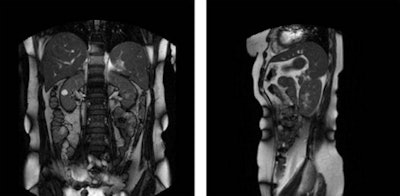

Left: Coronal and Right: sagittal time frame in 2D cine MRI. Image reproduced with permission from IOP Publishing.

Left: Coronal and Right: sagittal time frame in 2D cine MRI. Image reproduced with permission from IOP Publishing.The researchers concluded that the cranial caudal direction was the largest component of kidney motion. The smallest component proved to be the right-left direction, where a variation smaller than 1 mm over all breathing cycles was identified in one-third of the patients.